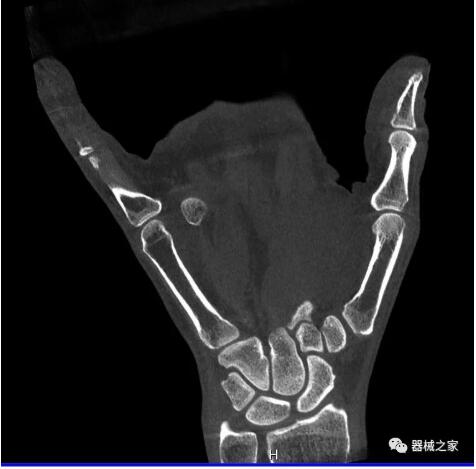

比如上面這款專用于足部和踝部掃查的CT成像系統(tǒng),患者在進(jìn)行CT掃查時(shí)只需要站在上面即可,雙腳站或者單腳站都可以,當(dāng)然,如果患者不是那么方便站著做完CT掃查,也可坐在上面。

這款CT掃查系統(tǒng)自帶屏蔽裝置,它的體積非常小,僅需要極小的空間即可,并不像常規(guī)CT那樣需要一間單獨(dú)的檢查室。此外,這種CT掃查的速度非???,僅需30秒左右可以完成檢查,輻射劑量相對常規(guī)的CT要少許多,尤其適合醫(yī)院的骨科使用。

而患者站著做足部或者踝部做CT檢查還有個(gè)好處是,可以檢查患者在負(fù)重的情況下,骨關(guān)節(jié)的真實(shí)情況,而躺著做CT掃查時(shí)未必能看出來。負(fù)重CT掃查特別是對于受傷的運(yùn)動員或者舞蹈員來說意義更大,能夠更準(zhǔn)確地評估傷情,幫助他們盡早復(fù)原。

以下是這些“特立獨(dú)行”的CT所拍出來的圖像: